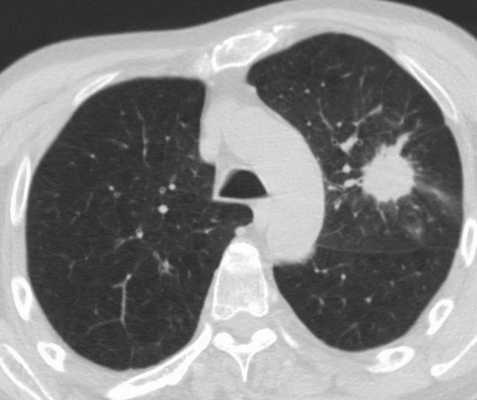

Метастатическое поражение легких